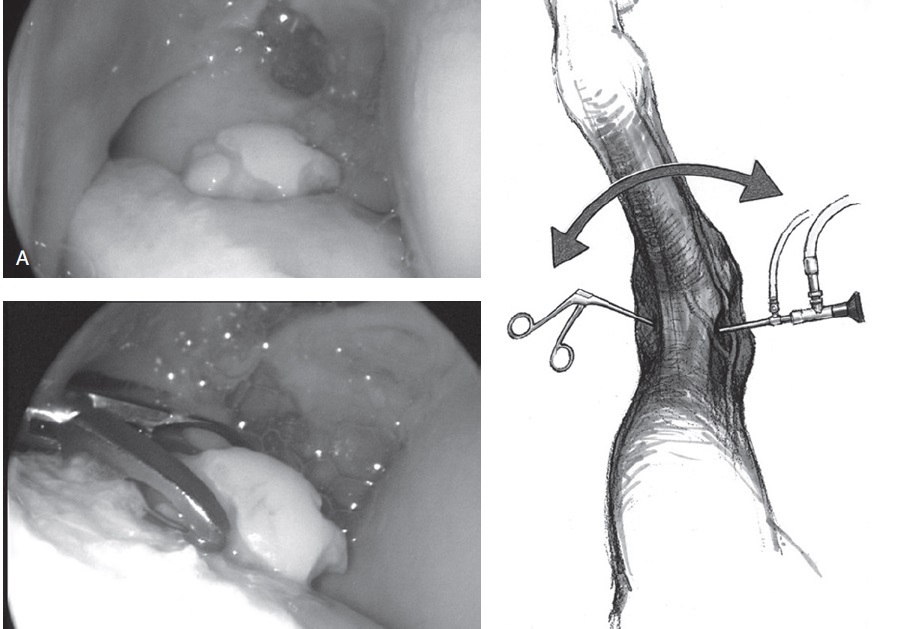

Figure 99-27. Arthroscopic view of a distal intermediate ridge OCD lesion using gas distension (A). The OCD fragment is removed from the distal tibia with the help of an Ethmoid rongeur (B). These OCD fragments are attached in most cases to the tibia by fibrous connective tissue. (C) Graphic illustration of the left tarsus showing the insertion of the arthroscope medially and instrument portal laterally in the dorsal pouch.